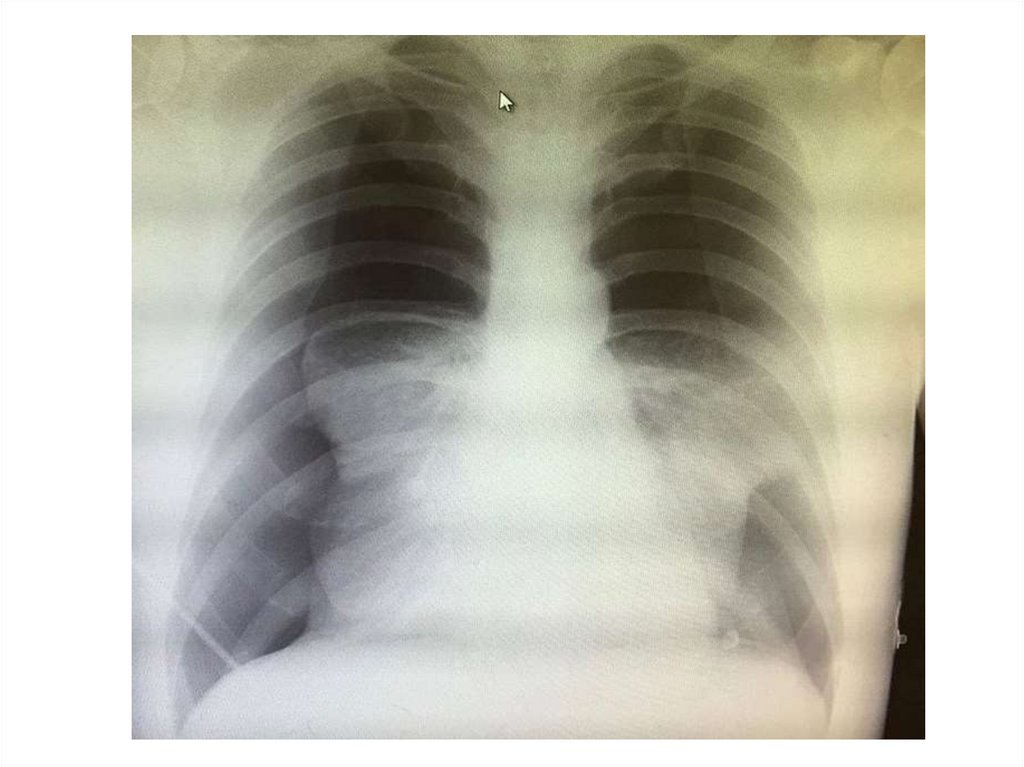

Воронкообразная деформация

грудной клетки

Индекс Хеллера

Индекс Гижицкой